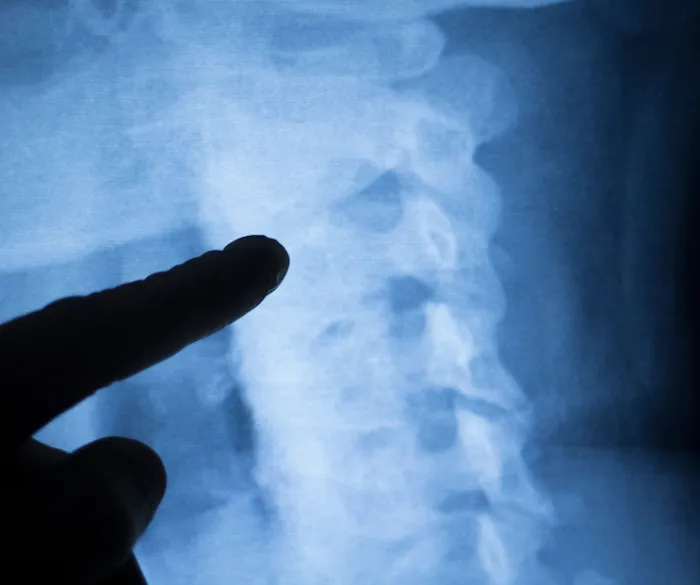

- Chiropractic Adjustments: Dr. Baldwin specializes in expert spinal adjustments and other manual therapies to alleviate pain, improve nerve function, and restore proper joint mobility. His goal is to help patients feel "faster and stronger" after each visit.

Sep 19, 2016 · Erika ReyesDr. B is amazing. I am a huge fan! I've got a bad back and he has totally helped me with both chiropractic and acupuncture treatments. I could not recommend him more highly!